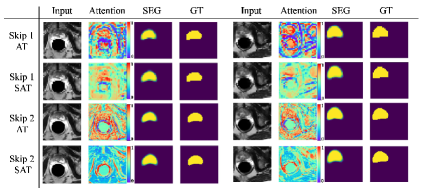

Note also that, although sometimes ST obtained almost similar results to SAT, the SAT transfers only one channel whereas ST results in transferring multiple channels (i.e. ST requires more parameters and involves higher memory usage). Similar to SAT, AT also transfers only one channel, however, as shown in Figures 6 and 7, AT tends to attend to wrong regions as it does not leverage the ST module to filter the most discriminative channels.

After the selected channels are transferred to the attention layer, the model learns to attend to the most important part(s) of the image, which helps in segmenting the target object(s) more accurately. A few samples of the attention maps for two of the proposed skip connections, used within the 2D U-Net (Fig. 6) and 3D V-Net (Fig. 7) architectures, are shown in Figs. 6 and 7 for the 2D skin lesion and 3D prostate MRI datasets. As can be seen in both Figs. 6 and 7, a model with only attention layer (i.e., only AT) tends to attend to several areas of the image; including both where the object is present and absent (note the red colour visible over the whole image). However, applying channel selection (i.e., ST) before the attention layer curtails the model from attending to less discriminative regions.

Advantages of channel selection and attention. For some experiments, we observed slight improvement in terms of Dice score when comparing the proposed method vs. only channels selection (or attention), but we argue that there are clear advantages in combining channel selection and attention because: 1) channel selection reduces the number of feature maps and more importantly enforces learning sparse representations, 2) channel selection alone outputs many channels which require more memory and more parameters to learn whereas the proposed method transfers only one channel (which is more interpretable) thus reducing number of network parameters and memory usage, 3) attention after the selection helps focusing on the most important spatial regions in the input, which is not captured by the channel selection part, however, attention without channel selection tends to attend to wrong areas as visualized above (Figures 6 and 7).